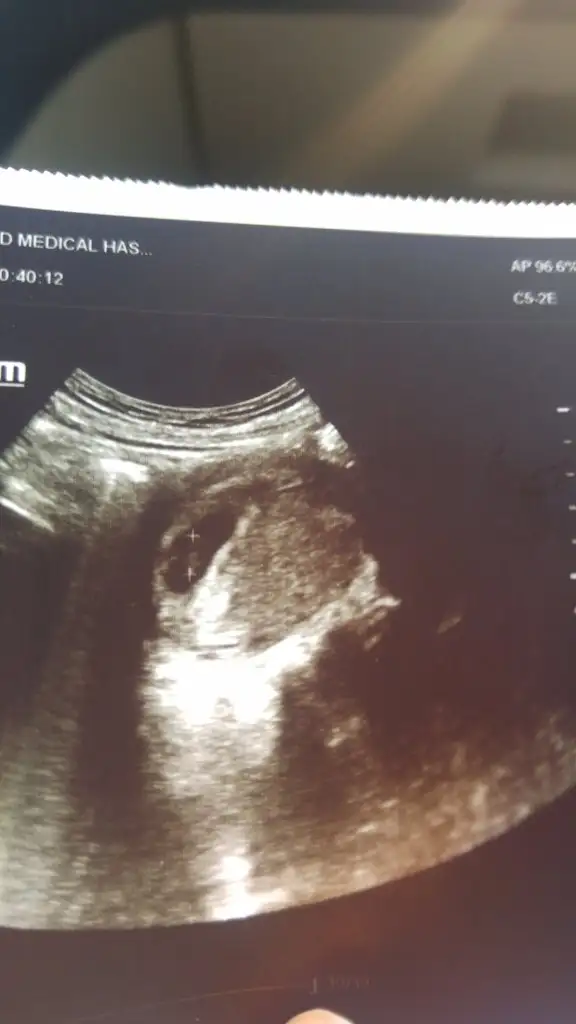

Kızlar ben minnoşumu gördümm kalbnide duydumm rabbm beklynn isteyen herkesse yaşatsnn çokk güzelll bir duyguymşş